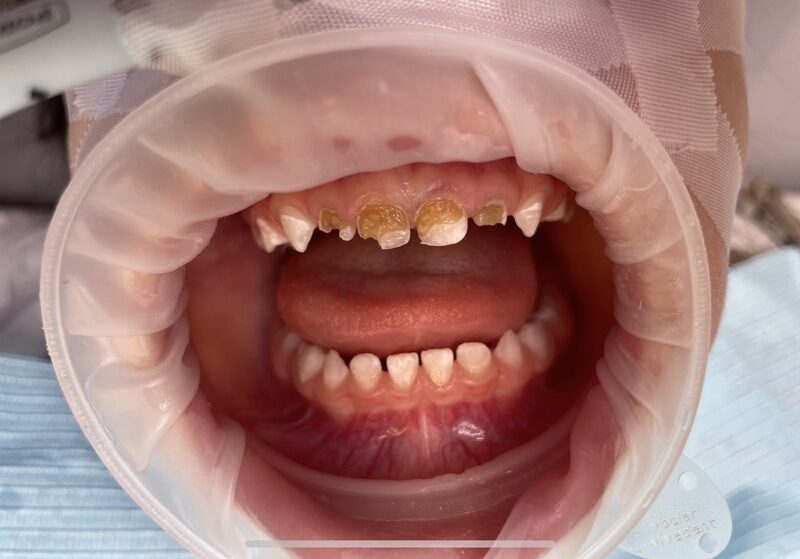

Situace se v některých oblastech zlepšuje, ale stále existuje velká skupina lidí, kteří péči o zuby zanedbávají. „Kazivost zubů je v Česku stále poměrně vysoká a řešení následků komplikované a drahé,“ dodává. Trend „rozevírajících se nůžek“ mezi těmi, kdo prevenci dodržují, a těmi, kdo zanedbávají, je patrný.

Jednoduché pravidlo „Čistý zub se nezkazí“ shrnuje princip prevence: kaz vzniká, když na zubech zůstává bakteriální plak. Pravidelné a důkladné čištění chrání zuby. Důležitá je i role rodičů: děti si zuby správně vyčistí samy až kolem deseti let, do té doby je třeba je učit a kontrolovat.

Ve Švýcarsku snížily dlouhodobé preventivní programy kazivost dětských zubů až o 90 %. V Česku se podobné programy, například projekt Dětský úsměv, snaží děti a rodiče učit správným návykům, ale často závisí na soukromých dárcích a sponzorech. Podle MUDr. Smažíka by plošná prevence stála jen zlomek toho, co nyní vydáváme na řešení následků kazu.